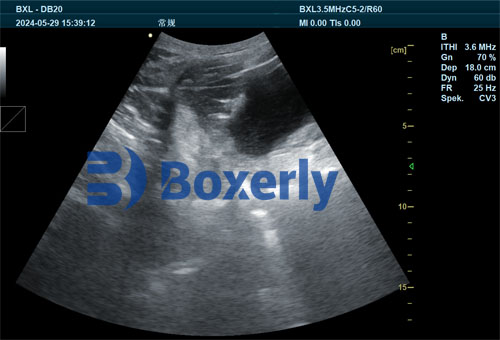

Ultrasound is a well-established imaging modality in both human and animal medicine. In swine production, its application spans from early pregnancy detection to evaluating uterine health and embryo development. For early-stage pregnancies—especially those in first-parity sows—ultrasound provides real-time visual and quantitative data on fetal structures, fluid accumulation, and uterine condition. This is especially useful for evaluating the effect of nutrition, which is known to influence embryonic survival, hormonal balance, and maternal immunity.

Real-time B-mode imaging: Essential for evaluating embryonic sacs, heartbeat detection, and uterine uniformity.

Many modern ultrasound machines are portable and user-friendly, making it feasible to integrate them into daily swine herd management. Models like the BXL-V50 and BXL-DZ20 are commonly used across pig farms and have become popular for their high image clarity and battery life in field settings.